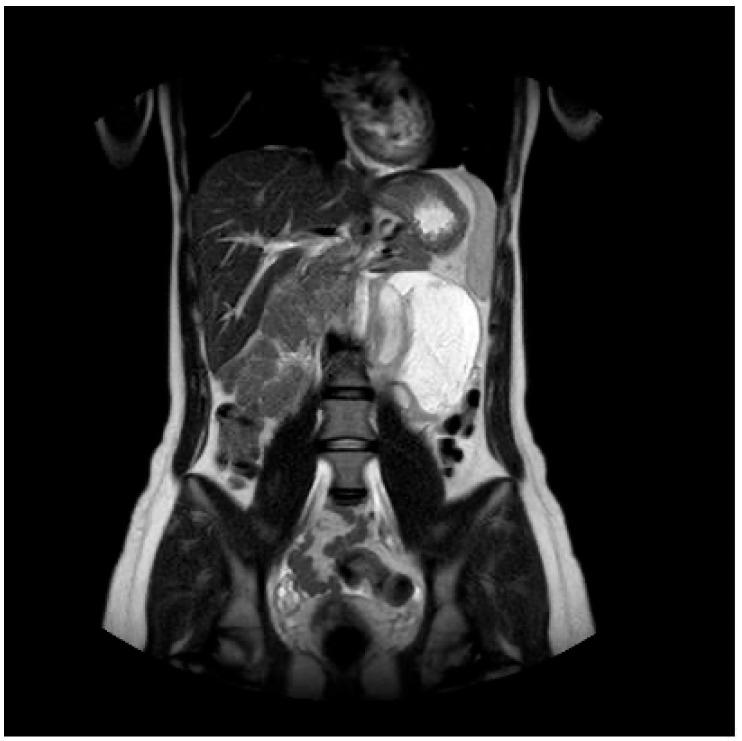

Retroperitoneal ganglioneuroma is a rare neuroectodermal tumor with a benign nature. We performed a literature review among 338 studies. We included 9 studies, whose patients underwent CT and/or MRI to characterize a retroperitoneal mass, which was confirmed to be a ganglioneuroma by histologic exam. The most common features of ganglioneuroma are considered to be a solid nature, oval/lobulated shape, and regular margins. The ganglioneuroma shows a progressive late enhancement on CT. On MRI it appears as a hypointense mass in T1W images and with a heterogeneous high-intensity in T2W. The MRI-"whorled sign" is described in the reviewed studies in about 80% of patients. The MRI characterization of a primitive retroperitoneal cystic mass should not exclude a cystic evolution from solid masses, and in the case of paravertebral location, the differential diagnosis algorithm should include the hypothesis of ganglioneuroma. In our case, the MRI features could have oriented towards a neurogenic nature, however, the predominantly cystic-fluid aspect and the considerable longitudinal non-invasive extension between retroperitoneal structures, misled us to a lymphatic malformation. In the literature, it is reported that the cystic presentation can be due to a degeneration of a well-known solid form while maintaining a benign character: the distinguishing malignity character is the revelation of immature cells on histological examination.

腹膜后神经节细胞瘤是一种罕见的良性神经外胚层肿瘤。我们对338项研究进行了文献综述。我们纳入了9项研究,这些研究中的患者接受了CT和/或MRI检查以对腹膜后肿块进行特征性描述,该肿块经组织学检查证实为神经节细胞瘤。神经节细胞瘤最常见的特征被认为是实性、椭圆形/分叶状以及边界规则。神经节细胞瘤在CT上表现为渐进性延迟强化。在MRI上,它在T1加权图像上表现为低信号肿块,在T2加权图像上表现为不均匀高信号。在综述的研究中,约80%的患者描述有MRI“漩涡征”。原始腹膜后囊性肿块的MRI特征不应排除实性肿块的囊性演变,并且在椎旁位置的情况下,鉴别诊断算法应包括神经节细胞瘤的可能性。在我们的病例中,MRI特征可能提示为神经源性性质,然而,主要为囊液成分以及腹膜后结构之间相当大的纵向无侵袭性延伸,使我们误诊为淋巴管畸形。在文献中,据报道囊性表现可能是由于已知实性形式的退变同时保持良性特征:区分恶性特征是组织学检查中出现未成熟细胞。